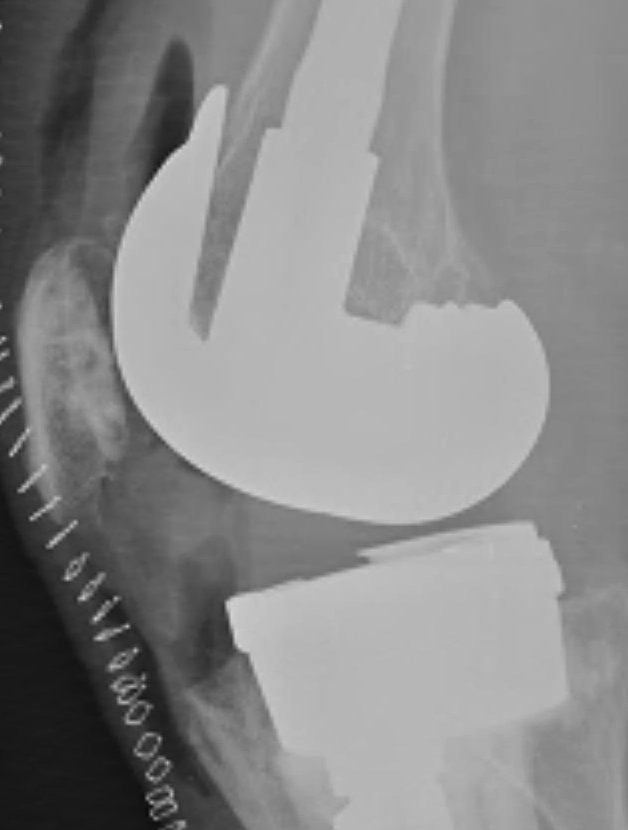

Removal of components

Remove poly

- implant specific tools

Careful removal implants to minimise bone loss

- thin, flexible osteotomes, micro-sagittal saw

- gigli saw

- can cut metal with carbide burr

Cemented femur / tibia

- separate at cement-implant interface

- remove cement later

Uncemented femur / tibia

- rarely have to cut base plate from keel (carbide burr)

- can perform TT osteotomy

- stacked osteotomes